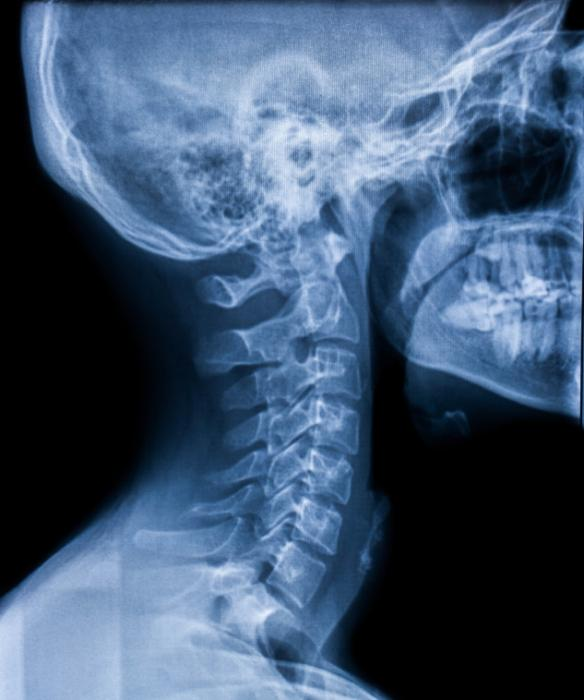

X-Rays

All the photos above are X-Photos and what we are seeing are the bones absorbing the rays because they are dense but your skin isn't that's why you only see bones and teeth